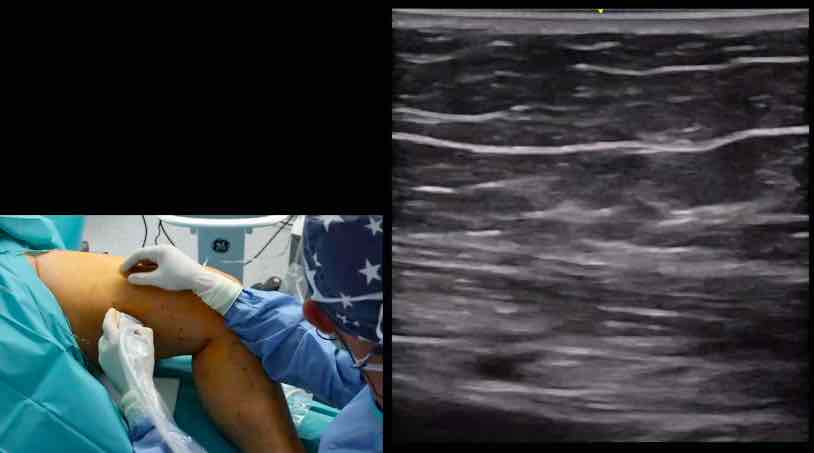

15. Freiburger Venen-Workshop – thumbnail 1 of 8 15. Freiburger Venen-Workshop – thumbnail 2 of 8 15. Freiburger Venen-Workshop – thumbnail 3 of 8 15. Freiburger Venen-Workshop – thumbnail 4 of 8 15. Freiburger Venen-Workshop – thumbnail 5 of 8 15. Freiburger Venen-Workshop – thumbnail 6 of 8 15. Freiburger Venen-Workshop – thumbnail 7 of 8 15. Freiburger Venen-Workshop – thumbnail 8 of 8

15. Freiburger Venen-Workshop

Live-Operationen - Endovenöse Technik sinnvoll einsetzen